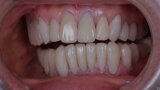

Figure 28 Post op left canine guidance

Figure 29 Post op canine guidance right side